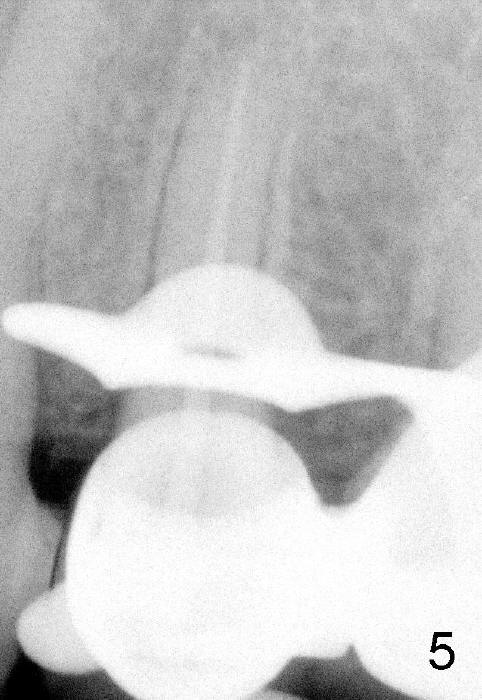

在倪先生五号牙根管治疗中,我们使用外科吸管,Apex locator很容易使用,插入主牙胶尖(图五),顺利完成根管治疗(图六)。